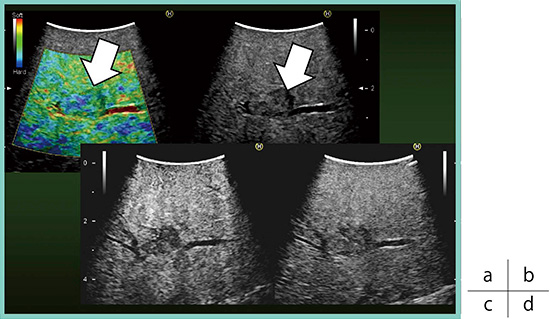

症例1は,大腸がんの肝転移でS3表面に病変がある症例である。RTEで,画面下部に表示されるインジケータを参考に適切な圧でプローブを当てると,病変は硬い腫瘍として青く表示された(図1b)。

図1 症例1:肝転移切除(S3)のRTE

症例2は,異時性単発の肝転移の症例である(図3)。腹腔鏡画像で肝表に突出した白い結節を確認したが,ICG蛍光像で内側に広がる蛍光領域が認められ,こちらが腫瘍本体であると考えられた。RTEでも,蛍光領域と同じ場所に腫瘍が認められた(図3b)。この症例は92歳と高齢のため非常に肝臓がもろく,腫瘍と周辺組織の硬さの差が大きいことから,RTEでは腫瘍が硬い結節として明瞭に描出された。

図3 症例2:肝転移切除(S7/8)のRTE